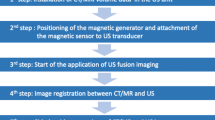

RFA Planning Session

Just before the main RFA procedure, RFA planning US examination was done by an operator (18 years of experience in RFA) with a clinical fellow or a senior resident in the ultrasound suite where the RFA procedure was performed. After planning examination, automatic fusion with US and CT/MRI images was attempted using an ultrasound system (Epiq 5, Philips, Best, the Netherlands) equipped with a 3D fusion software (PercuNav system, Philips, Best, the Netherlands) based on an electromagnetic tracking system that provides the position and orientation of the transducer and patient’s body in the transmitter’s spatial volume [10]. The real-time automatic fusion was achieved by matching the vascular structures in the US image to the correlating structures extracted from the CT or MRI images by auto-segmentation [10]. Automatic fusion was performed by sweeping US scans at the intercostal plane where the main and the right portal vein were observed. US scanning was performed for a maximum of 10 min and 7 times for registration, and failure was considered as inadequate registration after 10 min of attempts. Registration failure was defined as a technical failure due to poor vascular segmentation on US/CT/MRI, or misregistration for both central and peripheral structures > 3 cm. If the automatic fusion failed, manual fusion was performed for the RFA procedure. Repeated assessment of the localization confidence of the tumor, the safety of the approach route, the expected technical feasibility and the expected number of overlapping scans were performed by the operator and the assistant in consensus before and after the fusion process using a scoring system [1]. For the localization of the tumor, additional binomial scale assessment (poorly localized (score 1 and 2) vs. well localized (score 3 and 4)) was done for a more intuitive categorization. The quality of registration after fusion was assessed using a four-point scoring system. The details of the scoring system are provided in Table 1. Technical feasibility was assessed according to the safety of the route and the possibility of complete ablation.